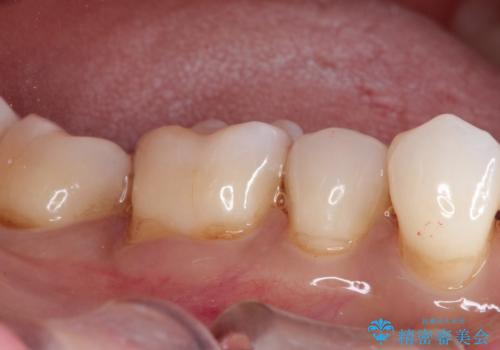

治療したむし歯の再治療。セラミックにしたい!

- 以前治療した歯が欠けたことを主訴に来院されました。

見た目もよく強度の高いものでの修復を希望されましたのでセラミックインレーにて修復しました。

当院でのセラミックインレーは歯とのつなぎ目を拡大鏡で確認して精度高く仕上げるため、むし歯のリスクを限りなく少なくできるよう治療します。